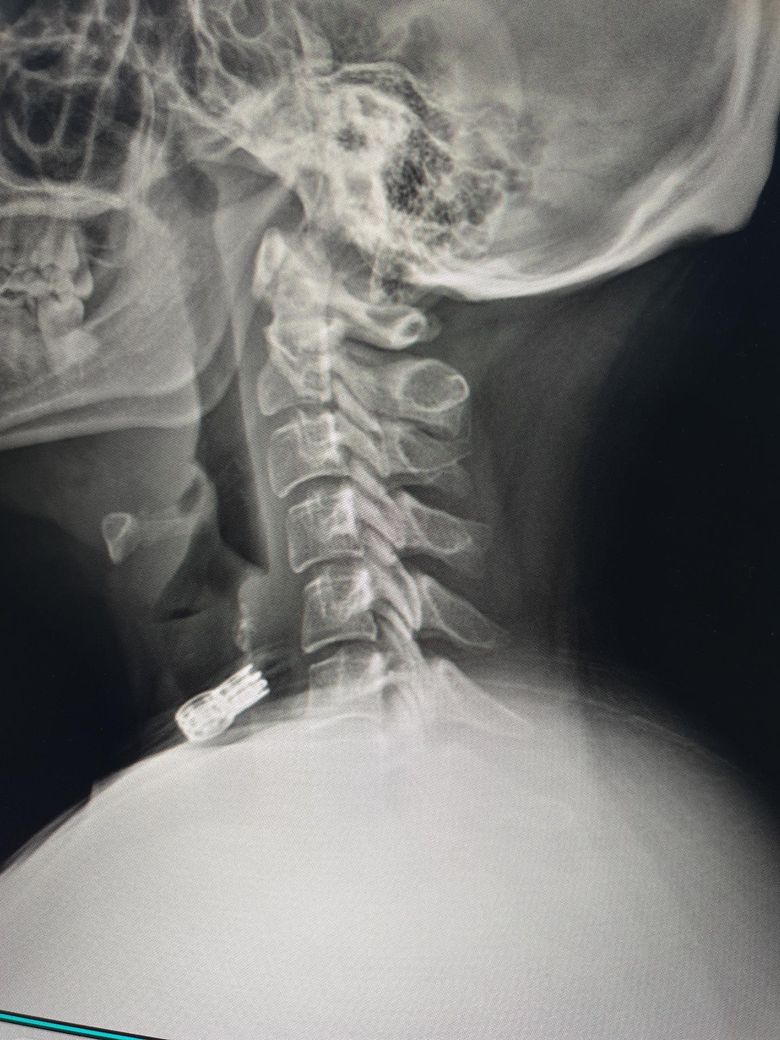

• 2번 째 사진

x-ray 상으로 보았을 때에는 일자목인 것으로 보입니다.

사진상으로 많은걸확인할수는없지만 일자목과함께 약간의 거북목을 가지고있는걸로 보이는데요 이는 굽은등과 평소 자세적인문제등에 의해서 나타날수있습니다~

엑스레이 사진을 보니 일자목 경향이 보이며 이로인해 목 뒤쪽 근육과 후두신경이 계속 긴장해 통증이 발생하는것으로 보입니다. 옆으로 누워 주무시는에 어깨가 말려있다면 어깨 높이를 충분히 받쳐주어 목이 아래로 꺾이지 않도록 유도하는 베개가 필수입니다. 4만원대 예산이라면 메모리폼이나 엘라스틱 소재의 경추형 베개중에서도 양옆이 가운데보다 높은 디자인이 좋습니다. 너무 말랑한것보다는 탄성이 있는 제품이 신경눌림 방지에더 효과적이며, 수건을 말아 목뒤에 받쳐보며 본인에게 맞는 높이를 먼저 테스트해보는것이 좋습니다. 답변이도움됐길 바랍니다!

• 제시된 측면 경추 X-ray를 보면 정상적으로 유지되어야 할 경추 전만(앞쪽으로 휘는 곡선)이 다소 감소되어 보입니다. 이런 경우 후경부 근육 긴장과 후두부 방사통, 말씀하신 신경이 뻗치는 느낌이 흔히 동반됩니다. 베개 선택이 증상에 직접적인 영향을 줄 수 있는 상태입니다.

핵심은 “높은 베개”가 아니라 “경추를 받쳐주는 구조”입니다. 현재처럼 어깨가 말리고 옆으로 주로 주무시는 경우라면 단순히 낮은 베개는 오히려 기도를 좁히고 근육 긴장을 악화시킬 수 있습니다.

옆으로 잘 때 기준으로는 어깨 두께를 채워서 머리와 척추가 일직선이 되도록 해야 합니다. 일반적으로 성인 여성 기준 압축 후 높이가 약 8에서 12cm 범위가 적절한 경우가 많습니다. 다만 중요한 것은 중앙이 꺼지는 형태가 아니라, 목을 받치는 부분이 살짝 더 높은 “경추 지지형” 구조입니다. 메모리폼이 무난하며 너무 푹 꺼지는 제품은 피하는 것이 좋습니다.

뒤로 누웠을 때 기준으로는 목 아래를 받쳐주고 머리는 약간 낮게 위치하는 형태가 이상적입니다. 즉, C자 형태로 경추를 지지해주는 베개가 적합합니다. 이런 구조가 없으면 현재처럼 후두부 통증이 지속될 수 있습니다.

정리하면, 옆으로 잘 때는 어깨 높이를 채우는 충분한 높이, 동시에 목을 따로 지지하는 경추 지지 구조, 너무 부드럽지 않은 소재가 기준입니다. 가격대 4만원이면 경추 지지형 메모리폼 제품 충분히 선택 가능합니다.

추가로, 통증이 가만히 있어도 지속되고 후두부에서 방사되는 양상이라면 단순 근육 문제 외에 후두신경통 가능성도 있습니다. 베개 교체 후에도 1주에서 2주 내 호전이 없으면 물리치료나 신경차단술 평가가 필요할 수 있습니다.